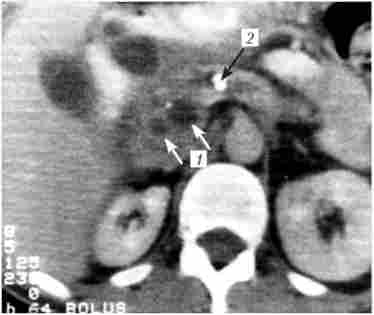

Комп'ютерна томографія при хронічному кальціфіцірующем панкреатиті. На знімку видно кісти головки підшлункової залози (У), розширений вірсунгов проток і кальцинат в його просвіті (2)

Мал. 20.7. Комп'ютерна томографія при хронічному кальціфіцірующем панкреатиті. На знімку видно кісти головки підшлункової залози (У), розширений вірсунгов проток і кальцинат в його просвіті (2)